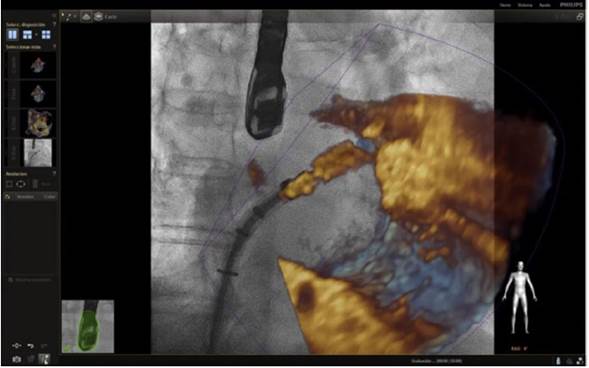

En respuesta a las necesidades de buenos resultados y seguridad para el paciente durante la realización de procedimientos complejos, se desarrolló un software capaz de fusionar la fluoroscopia y la ecocardiografía transesofágica 2D/3D13 en una sola imagen (figs. 2 y 3). Viene utilizándose cada vez con más frecuencia, con múltiples reportes en la literatura, pues ha mostrado sus buenos resultados de eficacia y especialmente de seguridad, dando la posibilidad de su implementación en la rutina diaria.

Figura 3 Imagen de fusión. Se observa paso de camisa en el septo interauricular comenzando giro hacia la válvula mitral para colocación de Mitraclip.